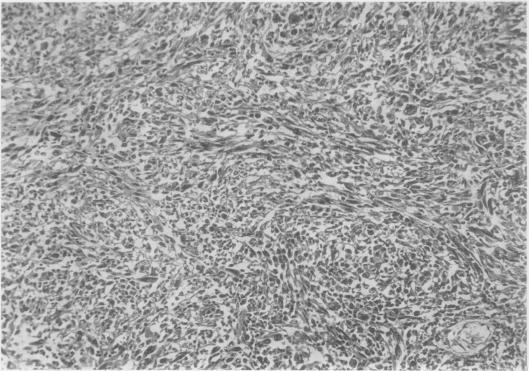

PRIMARY LEIOMYOSARCOMATA OF THE LUNG.

Thorax. 1965 Jan;20(1):13-7. doi: 10.1136/thx.20.1.13.